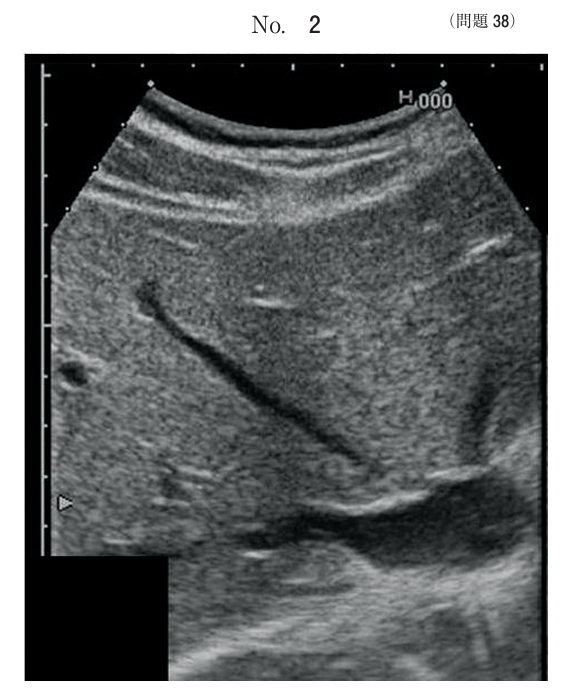

午前/問題38

腹部超音波画像別冊No. 2 を別に示す。

走査法はどれか。

1.左肋間走査

2.右肋間走査

3.右肋骨弓下走査

4.右季肋部縦断走査

5.心窩部 正中縦断走査